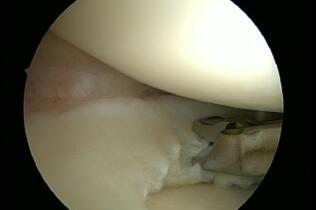

Meniscus Damage

The inner and outer meniscus serve to buffer the load and stabilise the joint. Damage to the meniscus can occur due to accidents, or wear and tear, or a combination of both. The consequences are pain, swelling, and possibly also entrapment. Meniscus damage occurs most frequently between the ages of 30 and 50. Men are affected twice as often as women (9 to 4.2/10000 respectively). If the damage is symptomatic, it can be repaired minimally-invasively by arthroscopy. The follow-up treatment depends on whether parts of the meniscus were removed (pain-adapted full weight-bearing) or whether the meniscus was sutured (usually partial weight-bearing). Unfortunately, only a few meniscus tears are suitable for suturing.